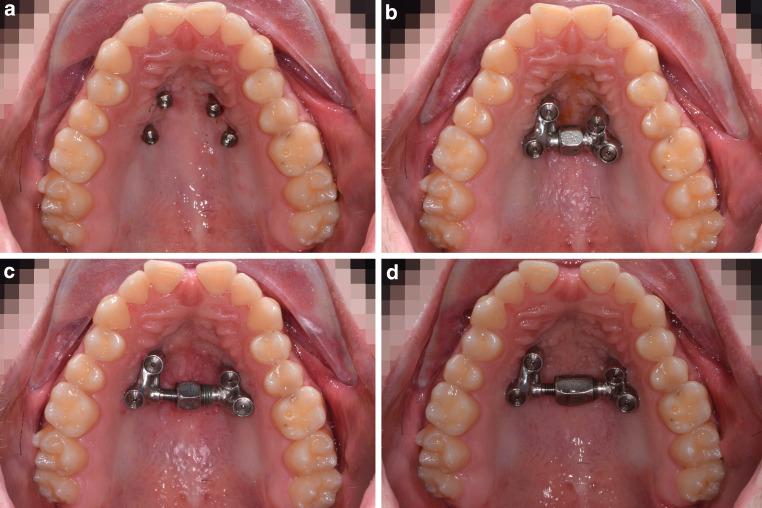

Procedure using CAD/CAM-manufactured insertion guides for purely mini-implant-borne rapid maxillary expanders.

With traditional rapid palatal expansion (RPE), orthopaedic forces are transmitted to the skeletal structures via the anchor teeth potentially leading to several unwanted dental side effects. To prevent these issues, tooth-bone-borne or purely bone-borne expanders were introduced using mini-implants in the palate. In this paper, the digitally planned Quadexpander is described which permits palatal expansion with only skeletal anchorage. The use of virtual insertion planning allows for insertion in areas of ideal bone, while avoiding roots and vital structures as well as the possibility of insertion into sites which would otherwise not be considered usable. A second advantage of digital planning is that mini-implants and the expander can be inserted in just one appointment.

传统的快速腭扩展术(RPE)通过锚固牙将矫形力传递至骨骼结构,这可能会导致一些不良的牙齿副作用。为防止这些问题,人们采用腭部微型种植体引入了牙-骨支撑式或纯骨支撑式扩弓器。本文介绍了数字化规划的Quadexpander扩弓器,它仅通过骨骼锚固实现腭部扩展。虚拟植入规划的应用使得扩弓器能够植入理想骨区域,同时避开牙根和重要结构,也避免了植入原本被认为不可用部位的可能性。数字化规划的另一个优势在于,微型种植体和扩弓器可以在一次就诊时完成植入。